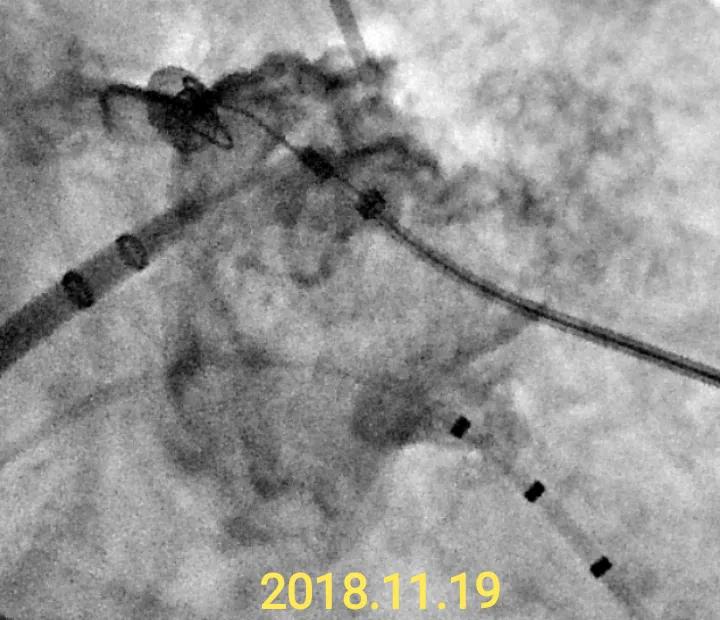

2018.11短程持续房颤做了房颤冷冻+左心耳封堵术(入组Leftear全国多中心临床研究),其中冷冻过程中发现肺静脉已经变细并且电位已经不太明显(提示这个房颤不是肺静脉相关,属于比较少见的10-20%比例),消融完后也没有去电复律。后来的左心耳封堵过程发现开口超大而且很浅,难度很大。因为我是Leftear封堵器的主要发明人之一,对这个性能比较了解。通过重新房间隔穿刺并且回收调整,并且最后用的25/37mm的特殊型号才成功封堵的(微量残余分流)。

封堵器植入